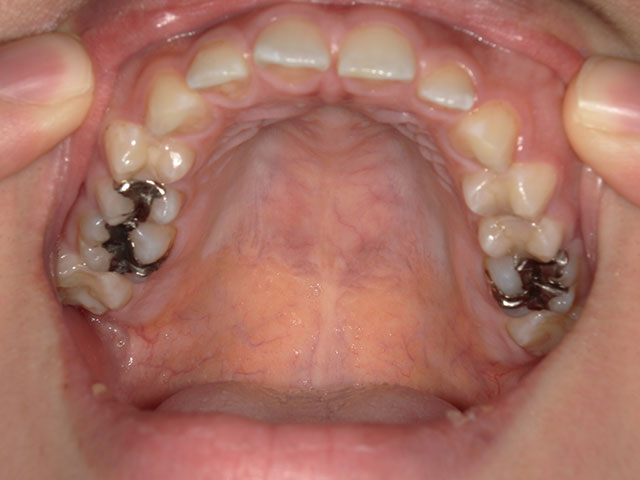

上顎の歯のお写真

今度は、またお友達やご家族にお手伝いいただき、上顎を下から撮影していきます。

ポイント:一番奥の歯までしっかり撮れていますと、診断の方がやりやすいです!